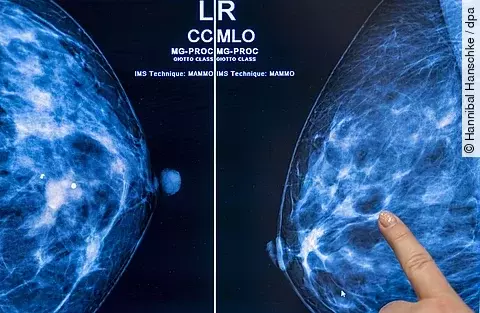

MammakarzinomMehr Brustkrebserkrankungen weltweit erwartet

Brustkrebs ist die häufigste Krebserkrankung bei Frauen in Deutschland. Zu den Risikofaktoren zählen etwa die Brustdichte, hormonelle Aspekte, familiäre Faktoren, aber auch Übergewicht und der Lebensstil. So handelt es sich neben solchen, die nicht beeinflussbar sind, also auch um vermeidbare Risikofaktoren.

Mammakarzinom: Risikobasiertes Screening oder jährliches Screening?

Anders als beim herkömmlichen Brustkrebsscreening berücksichtigt das risikobasierte Brustkrebsscreening das individuelle Risiko der jeweiligen Patientin. Es findet in angepassten Intervallen statt und bereits seit einiger Zeit wird die Frage diskutiert, ob es eine Alternative zum jährlichen Screening sein kann. Genau diese Frage stand jetzt im…